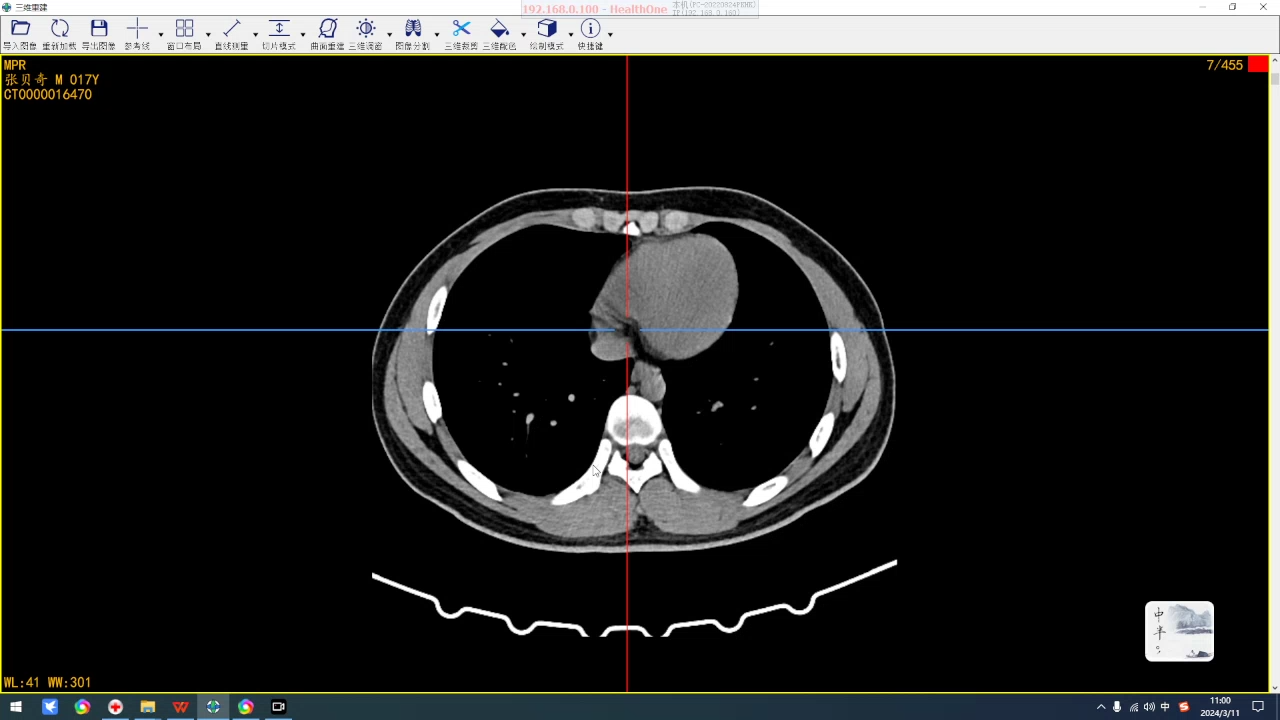

简要病史:右侧耻骨下肢骨折及右手掌骨骨折来来诊。

全腹部是刚入院第二天的检查,盆腔是入院检查。

下午复查的后,脐区腹直肌后方的包块比早上有缩小,这会不会是一种疝?